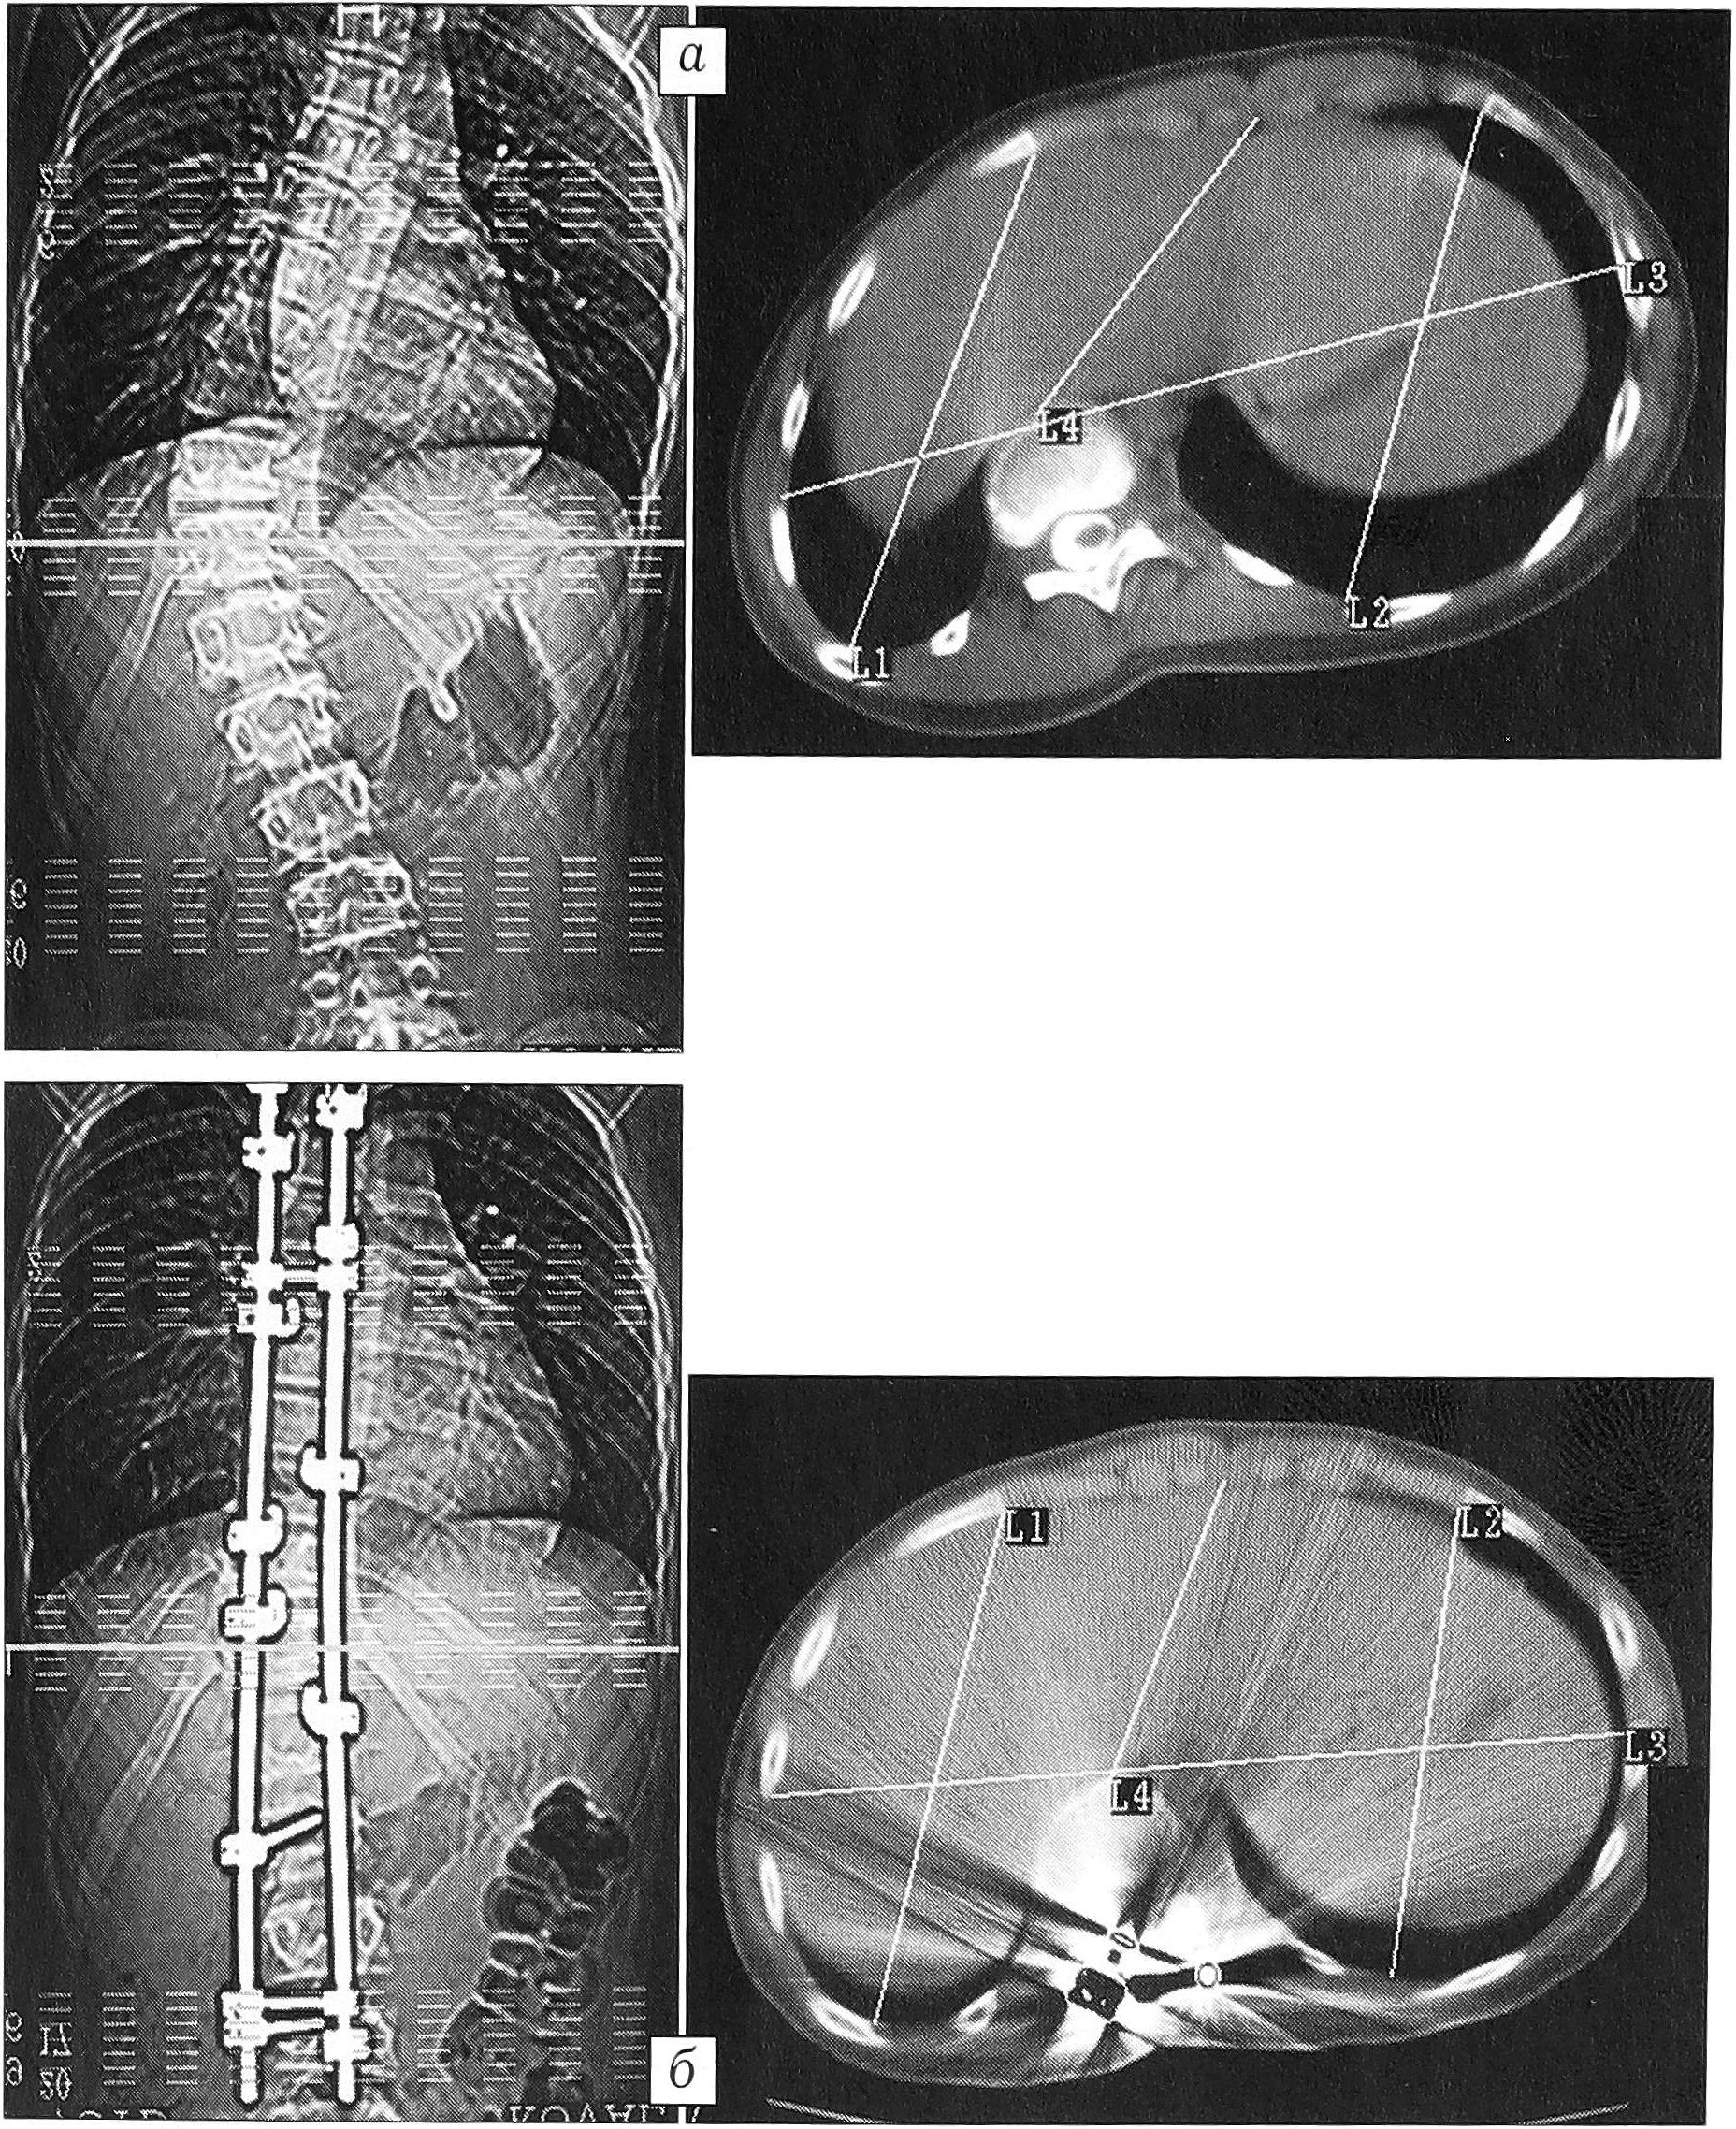

Рис. 3. Рентгенограмма позвоночника и КТ больного А. с левосторонним грудным сколиозом: величина общего угла основной дуги искривления 128°, ротация позвонка 45°.

Рис. 4. КТ больной К. с правосторонним грудным сколиозом до (а) и после (б) оперативного лечения. Деротация вершинного позвонка 17° (70,8%).

Нотация вершинного позвонка, измеренная относительно верхнего нейтрального, до операции равнялась в среднем 24,85°, т.е. была сравнима с абсолютной. После оперативного лечения она составила 18° — разница 6,85° (27,56%), что несколько больше соответствующего абсолютного показателя. В целом полученная коррекция ротации у каждого пациента несколько больше, поскольку верхний нейтральный позвонок, относительно которого проводятся измерения, также меняет свое положение в пространстве. В одном случае абсолютная деротация вершинного позвонка составила 5° (19%), а относительная — 11° (48,8%), что было связано с увеличением ротации вершинного позвонка на 6° (рис. 5).

Рис. 5. КТ больного В. с правосторонним грудным сколиозом до (а—в) и после (г—е) оперативного лечения. б, д — верхний нейтральный, в, е — вершинный позвонок.

Среднее абсолютное значение ротации, измеренной в горизонтальной плоскости, до оперативного лечения составило 24,5° (в группе больных с углом менее 80° оно равнялось 22,36°, с углом более 79° составляло 30,75°). Максимальное значение ротации, равное 45°, выявлено у больного А. с левосторонним грудным сколиозом с максимальной в исследуемой группе величиной общего угла основной дуги — 128° (рис. 3). После оперативного лечения среднее абсолютное значение ротации, измеренной в горизонтальной плоскости, составило 21,5° (19,5° у больных с углом деформации менее 80° и 30,0°— с углом более 79°), т.е. разница с предоперационным значением находится в пределах ошибки метода. Максимальная деротация, равная 17° (70,8%), получена у пациентки К. с диспластическим правосторонним грудным сколиозом. Существенная величина деротации позволяет считать ее истинной (рис. 4).